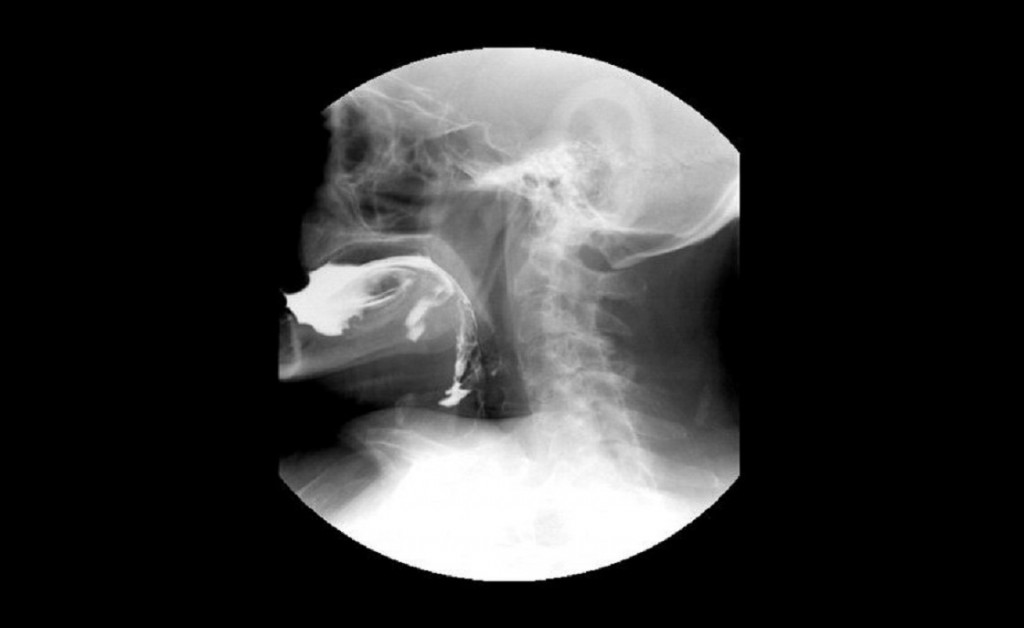

La gestión local brinda este servicio de imágenes de rayos X para evaluar la deglución y advertir dificultades en la misma. Esta asistencia médica amplía la capacidad de atención y beneficia la recepción de niños y niñas.

En el Hospital Materno Infantil de Tigre, el Municipio incorporó un nuevo estudio de videodeglución en el servicio de imágenes de rayos X para evaluar la deglución y advertir dificultades en la misma. Esta prestación médica amplía la capacidad de atención y mejora la recepción a niños y niñas.